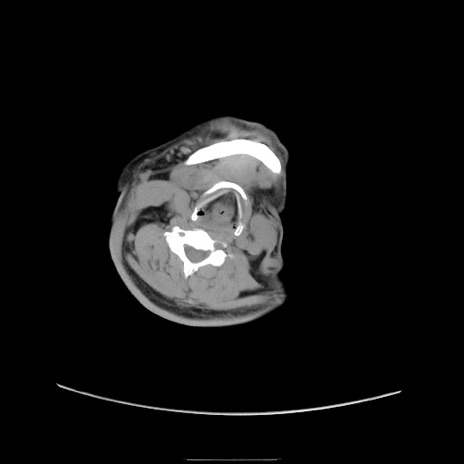

症例22(横断像)

【症例】50歳代男性

【主訴】腹痛

【現病歴】AVMからの被殻出血のため回復期リハ病棟入院中。 本日午後3時頃急に下腹部痛が出現した。

【既往歴】AVM、被殻出血、虫垂炎、高血圧

【身体所見】意識晴明、左半身不全麻痺、会話の理解は良好、36.5°C、腹部:膨隆、全体に板状硬、下腹部正中に圧痛点あり、反跳痛-、筋性防御不明、右下腹部にope scar

【データ】WBC 9400、CRP 0.06